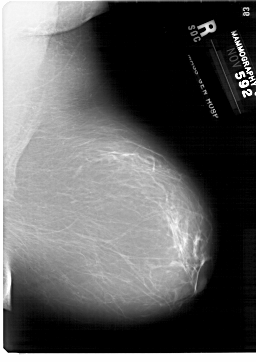

A_1876_1.RIGHT_MLO

RIGHT_MLO LINES 6871 PIXELS_PER_LINE 4861 BITS_PER_PIXEL 12 RESOLUTION 43.5 NON_OVERLAY